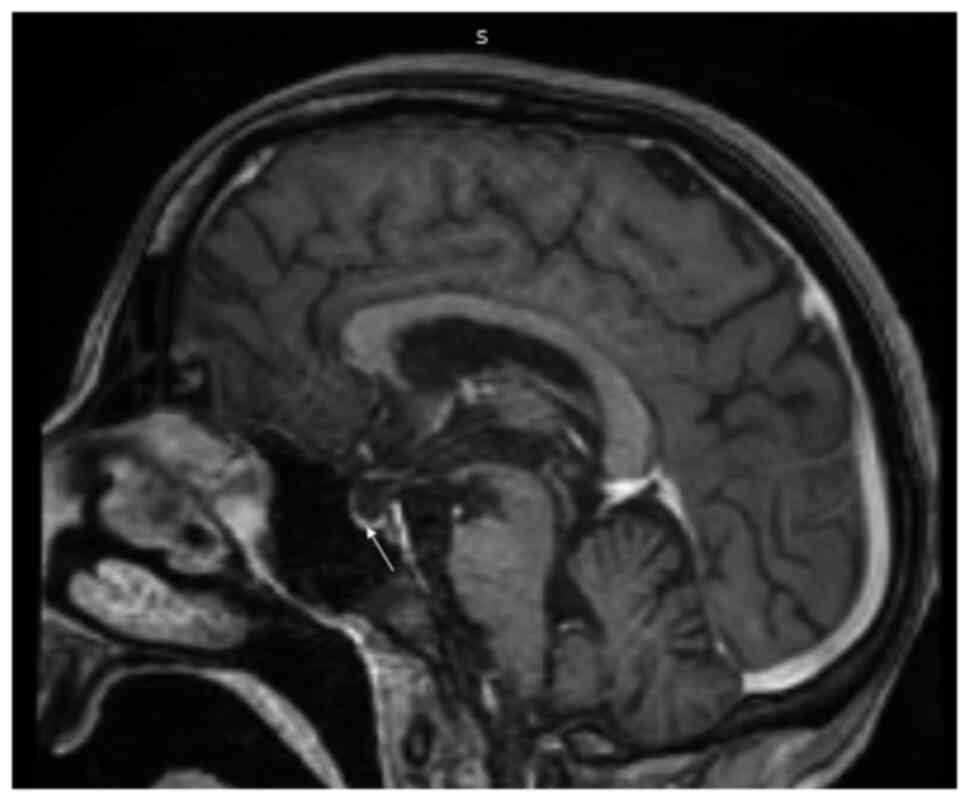

An analysis revealed that her haemoglobin level was 106 gm/l (normal range, 120-150 gm/l), the total leucocyte count was 4.1x109/l (normal range, 4-10) and her platelet count was 90,000/mm³ (range, 1.5-4.5 lakh); the differential counts were: Polymorphs, 88%; lymphocytes, 10%; eosinophils, 1%; monocytes, 1%; erythrocyte sedimentation rate, 40 mm/1st hour; random blood glucose, 4.662 mmol/l; urea, 7.14 mmol/l (normal range, 4.64-16.06 mmol/l); creatinine, 33.5 µmol/l (normal range, 35.36-106.08 µmol/l); serum sodium, 120 mmol/l (normal range, 135-155 mmol/l); serum potassium, 4 mmol/l (normal range, 3.5-5.5 mmol/l); aspartate aminotransferase, 56 IU (normal range, 5-34 IU); alanine aminotransferase, 53 IU (normal range, 6-40 IU); and alkaline phosphatase, 73 IU (normal range, 15-112 IU). Scrub and dengue serology were negative. HBsAg, hepatitis C virus and HIV serology were non-reactive. The results of a urine examination, chest X-ray and ultrasound abdomen were all within normal limits. Her arterial blood gas analysis, cerebrospinal fluid examination and electroencephalogram were within normal limits. Given her history of altered sensorium, the delayed relaxation of deep tendon reflexes, bradycardia and hyponatremia, myxedema crisis was suspected and her myxedema score was calculated. Her myxedema score was 75, suggesting myxedema crisis. Thyroid function tests revealed that T3 was <0.616 nmol/l (normal range, 1.08-3.14 nmol/l), T4 was 39.12 nmol/l (normal range, 64.35-141.57 nmol/l) and thyroid stimulating hormone (TSH) was 1.14 mIU/l (normal range, 0.550-4.780 mIU/l), suggestive of secondary hypothyroidism as opposed to sick euthyroid syndrome. Since there was a history of lactation failure, secondary amenorrhea and the delayed relaxation of deep tendon reflexes, the possibility of secondary hypothyroidism was kept. Samples for the pituitary hormonal profile were sent and management for the myxedema crisis was initiated. The patient was managed with oral levothyroxine 500 µg stat followed by 100 µg once daily through a Ryle's tube, hydrocortisone infusion, intravenous fluids, injectable antibiotics and rewarming. Her pituitary hormonal profile was suggestive of panhypopituitarism [prolactin, 76.08 pmol/l (normal range, 145.21-1,161.73 pmol/l); adrenocorticotropic hormone, 1.30 pmol/l (normal range, 1.58-13.92 pmol/l); cortisol, 108.98 nmol/l (normal range, 120.18-626.75 nmol/l); luteinising hormone, 5.4 IU/l (normal range, 1.9-12.5 IU/l); follicle stimulating hormone, 3.11 IU/l (normal range, 3.85-8.78 IU/l); and estradiol, 36.71 pmol/l (normal range, 71.58-528.62 pmol/l)]. The hormonal profile of the patient is presented in Table I. The patient exhibited an improvement in bradycardia, hypotension and hyponatremia over the ensuing 4 days; however, there was no improvement in the altered sensorium. She was awake, but not able to speak or move her limbs. A repeat neurological examination was performed, which revealed cogwheel rigidity and paraparesis. The possibility of acute parkinsonism was kept. Magnetic resonance imaging of the sella and brain was suggestive of an empty sella and extrapontine myelinolysis (Figs. 1 and 2), substantiating the diagnosis of Sheehan's syndrome with acute parkinsonism. The patient was commenced on levodopa/carbidopa following which there was a partial improvement in symptoms. She was discharged on oral hydrocortisone, levothyroxine, ethinyl estradiol and progesterone, and physiotherapy was recommended. At the 6th month of follow-up, the patient was communicating well, the paraparesis had improved and she could perform all household activities.

Figure 2

Magnetic resonance imaging (sagittal view; T1W with contrast) illustrating an empty sella (arrow).